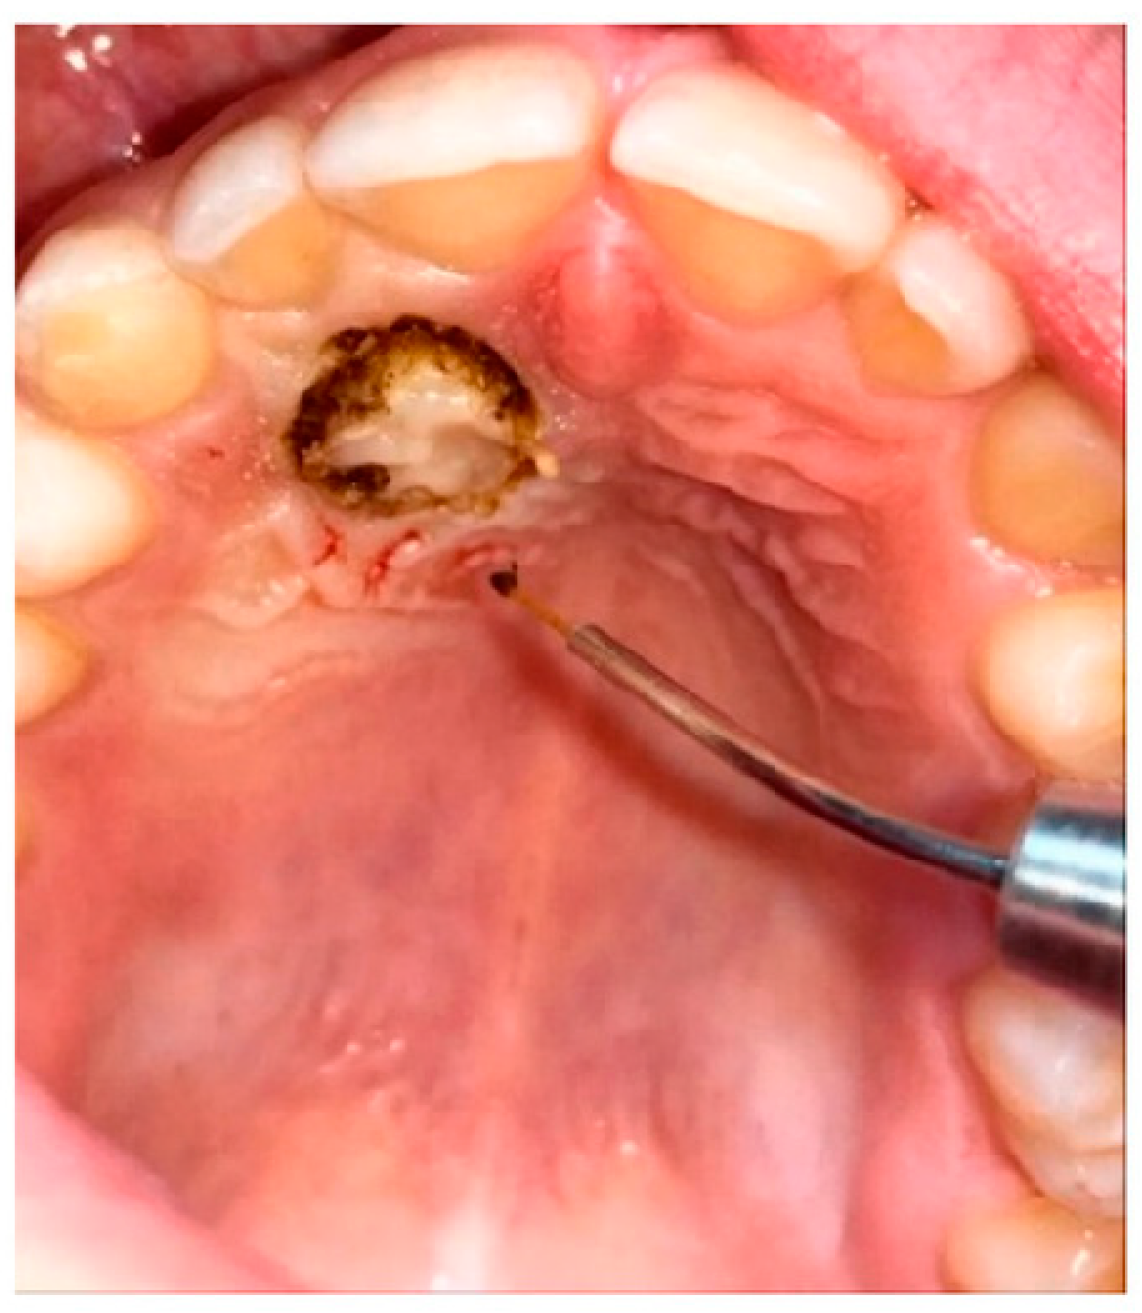

All patients underwent disinclusion surgery using a diode laser (Ka-Laser Blue Derma. Eltech K-Laser srl, Treviso, Italy) with wavelengths of 445 nm, 660 nm, and 970 nm. The laser was operated in continuous wave mode at a power output of 4 watts. The energy density (fluence) applied ranged from 0.5 to 8 J/cm2, tailored to tissue thickness and surgical requirements. Each application lasted between 15 and 30 s per treated site to ensure effective ablation and hemostasis while minimizing thermal damage. The focused laser beam allowed precise incision and coagulation, reducing operative trauma and promoting faster postoperative healing. All procedures were performed by the same operator, who performed an operculectomy using the high-intensity laser; if necessary, ostectomy was performed using a low-speed handpiece and under copious irrigation. At the end of the procedure, a periodontal pack (Coe-Pak, GC Dental, Tokyo, Japan, regular periodontal dressing, base 90 g + catalyst 90 g) was placed to protect the treated area of the palate, and it was removed after seven days. To assess the spontaneous eruption of canines, no orthodontic anchorage or traction was applied to all exposed canines (Figure 4).

Figure 4.

Diode laser disinclusion (diode laser K-Laser, Eltech, Blue Derma, 445–660–70 nm).